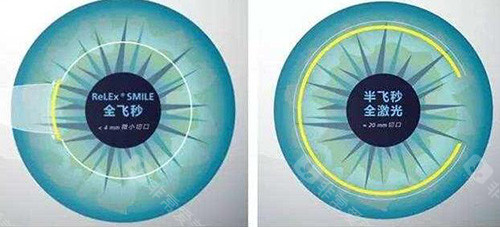

全飞秒激光手术:15800元/双眼